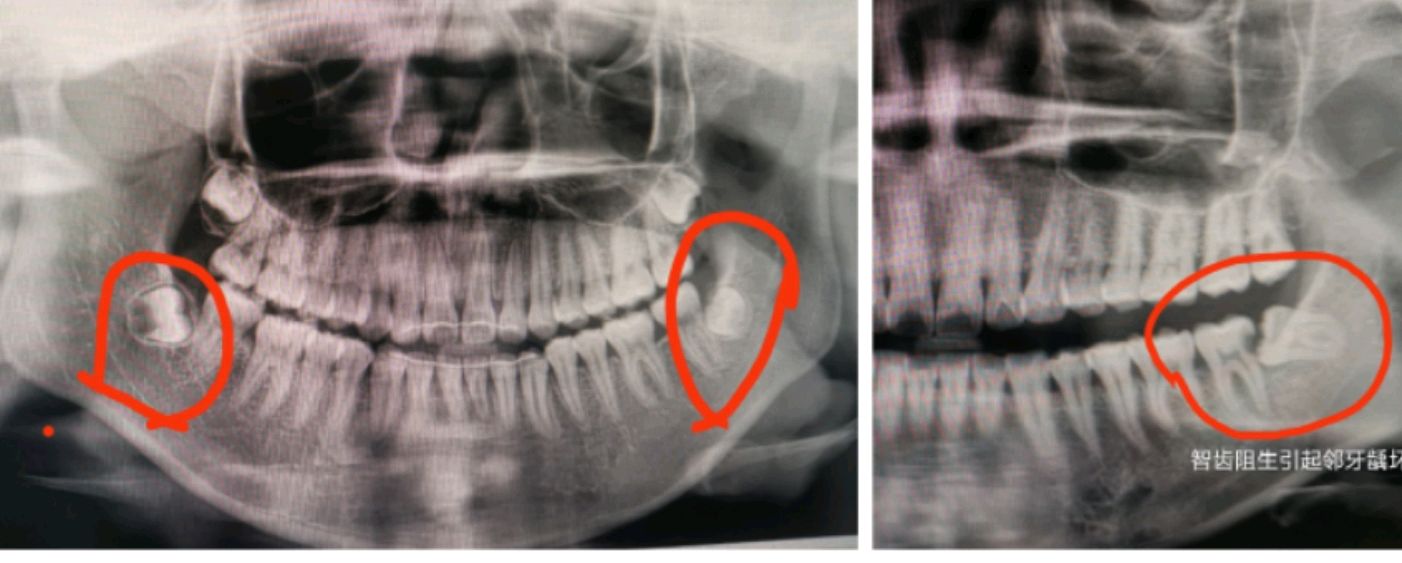

2、有的智齿本身已有症状或病变,对周围牙、牙龈或骨组织已产生或将产生不良影响和病变,通常情况下需要拔除;有的正畸需要,建议拔除;

举例的图示智齿都要建议及早拔除